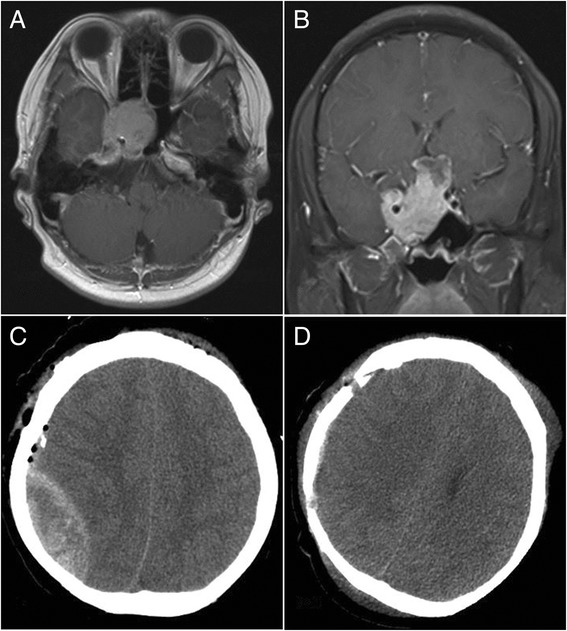

Fig. 1.

Ipsilateral remote hemorrhage in case 1. a, b Preoperative-enhanced magnetic resonance imaging (MRI) revealed a sellar tumor and normal ventricular size with no expansion. c CT revealed an epidural hematoma behind the surgical field after the tumor resection. d CT showed that the hematoma had been cleared